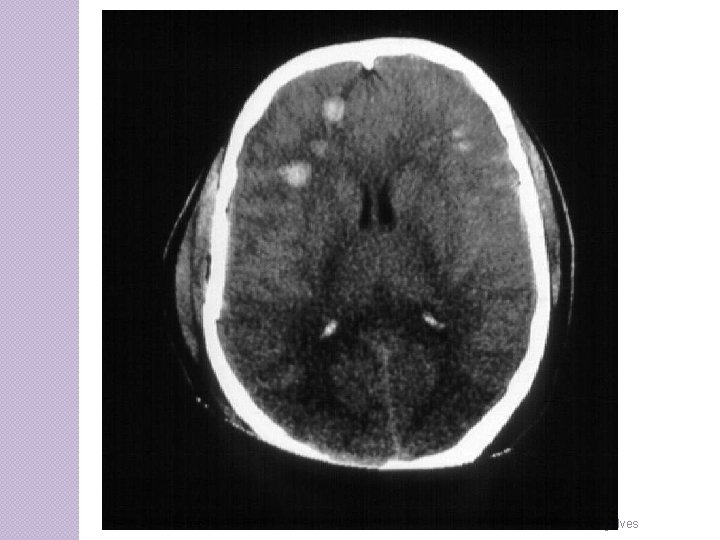

CLASSIFICAÇÃO Lesão axonal difusa � Coma pós-traumático prolongado (dias a semanas) • Não resultante de lesão de massa ou lesões isquêmicas. • Lesões de alta velocidade com estiramento ou chacoalhamento do tecido cerebral � Evidências de decorticação ou descerebração � Caso sobrevivam gravemente incapazes. � Lesões microscópicas: Mini hemorragias (petéquias) em substancia branca � Geralmente exibem disfunção autonômica, como HAS, hiperhidrose e hiperpirexia. � Edema cerebral e aumento da PIC � Mortalidade em 30 a 40 %

CLASSIFICAÇÃO CONTUSÕES ◦ Manifestações dependem da área lesada ◦ Lesões golpecontragolpe principalmente frontal e occipital ◦ 20 % evoluem para hematomas cirúrgicos

CLASSIFICAÇÃO CONTUSÃO CEREBRAL